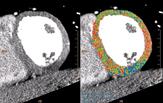

While no hypo-dense regions were observed in the myocardial territories of the LAD, they were present in the basal- and mid-inferior regions of the myocardium (RCA-PLB territories). This is exhibited in the short-axis representation (Figure 3), with the original grayscale images shown on the left, and the corresponding defect probability color representation on the right – the gradient of the color maps represents a range of the myocardial regions that are normal (red) to the hypo-dense regions (blue).

Figure 4(a), rotated to show the RCA-PLB territories, displays the coronary artery tree superimposed on the “egg-shell” color map representation of the LV, with blue indicating hypo-dense regions. Figure 4(b) shows the polar maps representing the short-axis segmentation of LV with the color map overlay using the defect probability method.